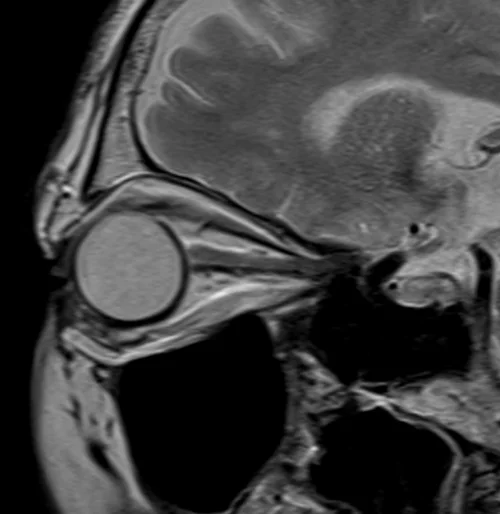

MRI Orbits T2 sagittal oblique images